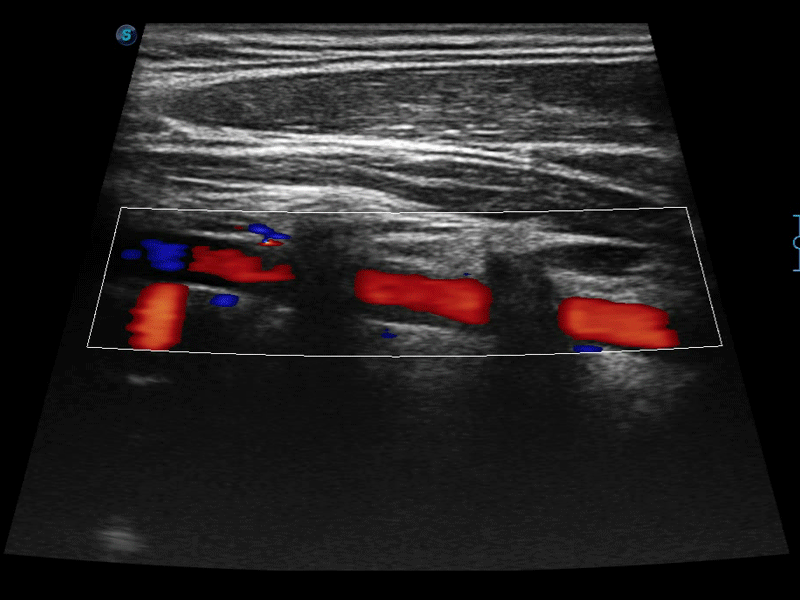

高分辨率血流成像技術(shù)提高了對低速血流信號的檢測能力。在提高空間分辨率的同時,也克服了血流外溢現(xiàn)象,為用戶提供更加真實的血流動力學(xué)信息。

通過色彩血流和實時寬景相結(jié)合,可觀察到完整的靜脈或動脈的血流,方便醫(yī)生檢查。實時掃查過程中,如有任何操作失誤也可以很容易地進行回掃擦除,而不會中斷掃查。